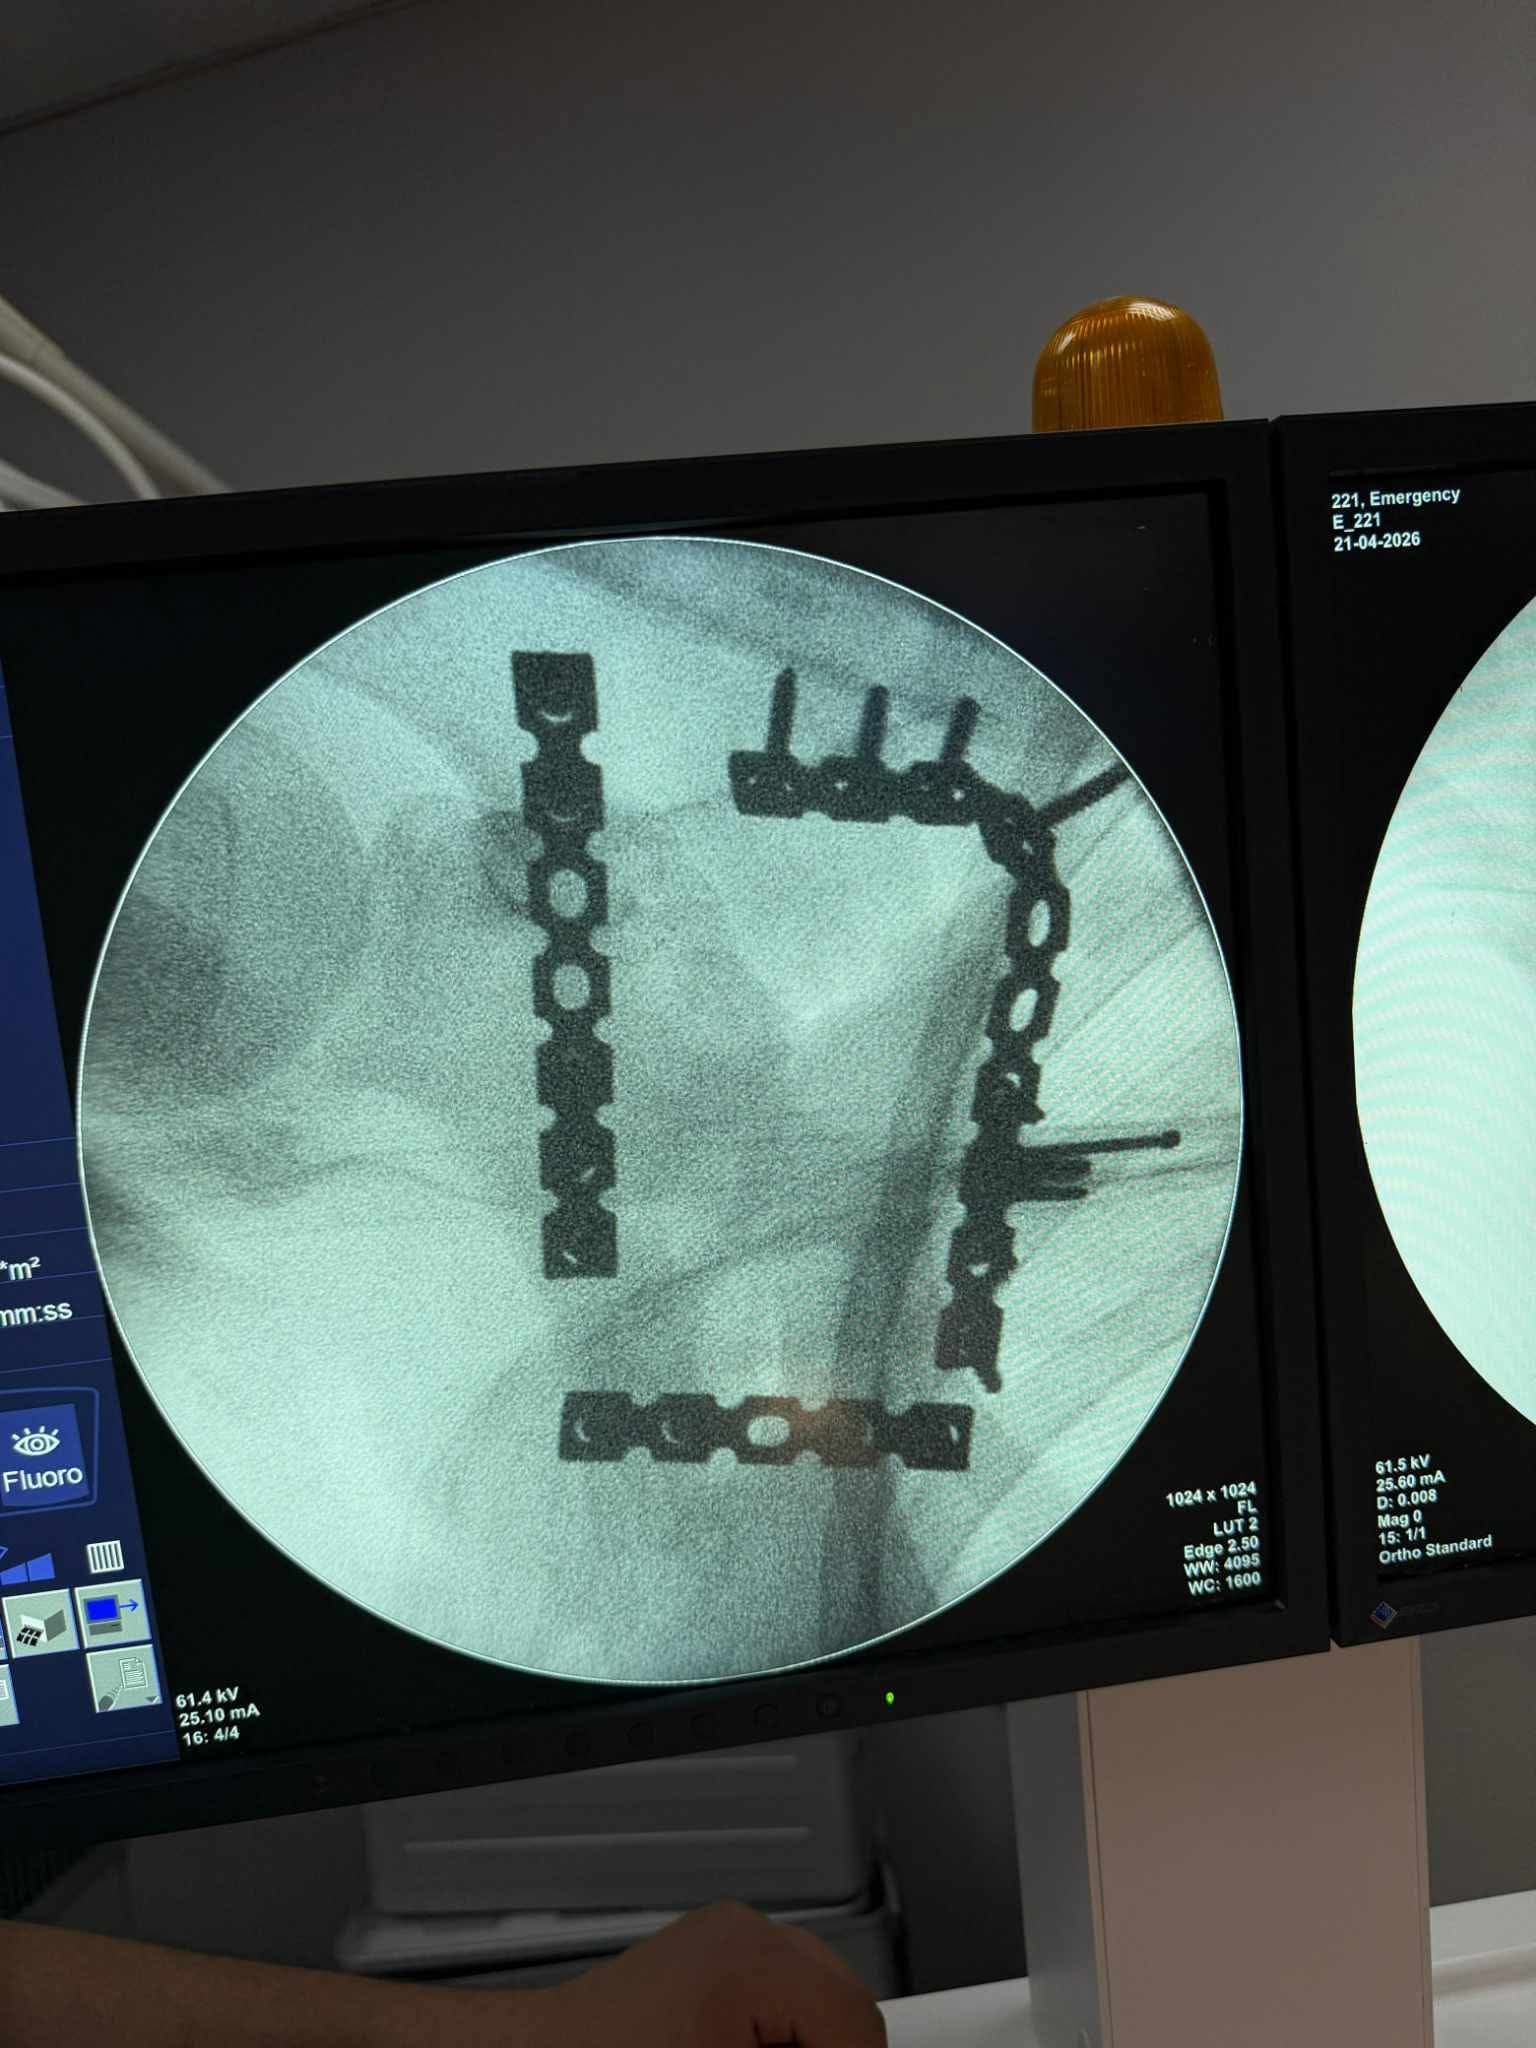

كان استقبل مستشفى التأمين الصحي بالفيوم شابًا يبلغ من العمر 17 عامًا، يعاني من كسر مفتت بعظمة لوح الكتف (Scapula)، وهي من الإصابات الدقيقة التي تتطلب مهارة عالية وتدخلًا جراحيًا متخصصًا.

خضع المريض لعملية جراحية معقدة استمرت نحو 4 ساعات تحت تأثير التخدير العام، تم خلالها رد وتثبيت الكسر بإستخدام الشرائح والمسامير.